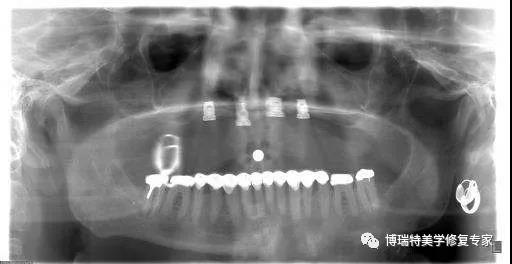

在软组织切开的过程中常可出现出血,黏骨膜剥离损伤大、黏膜下剥离广泛、术后压迫不良、钻孑L过深伤及-l齿槽血管、颌骨内肿瘤破裂等是发生出血的常见原因。如受全身因素影响如患者患有出血性倾向疾病时,手术时也可发生出血。术中出血除造成出血过多外,若血液倒流人口底,还可能阻塞呼吸,导致窒息。为了避免术中出血,种植手术时应尽量减小创伤,术前应拍摄X线曲面断层片,了解下颌管的位置及走行,设计好种植体的植入深度及植入方向,避免损伤下牙槽血管。

为了避免上颌窦穿通,种植牙手术前应拍摄X线片,并以此为依据选择好适当的种植体,确定植入深度。若上颌窦位置过低时,可行上颌窦提升术,后再植入种植体。在某种情况下还可以避开上颌窦行冀上颌区种植。小的穿孔不需特殊处理,可在穿孔处放置明胶海绵以封闭穿通口,较大的穿孔较易引起种植体周围炎,需进行黏膜修补后再植人种植体,对于出血严重的病例,还应行上颌窦开窗术,止血后封闭窦底穿孔。

对下牙槽神经或颏神经的牵拉而导致的神经功能障碍,症状一般会逐渐减轻,通常在6个月内可完全恢复。若为种植体末端压迫所导致的神经功能障碍,在摄片并排除其他病因后,应立即取出种植体。另外神经走行路径中的肿瘤压迫也会导致相应的神经功能障碍,此时应及时诊断,对症处理。对于种植术所导致的神经损伤,4~6个月内未进行及时处理会导致神经功能的退化,因此应进行早期处理,在神经损伤一个月内进行。为防止术后神经功能障碍,术前应拍摄X线全景片,对颌骨的高度进行精确的测量,选择合适的种植体,确定种植体植入深度,种植体末端距下颌神经管2 mm距离为安全距离。